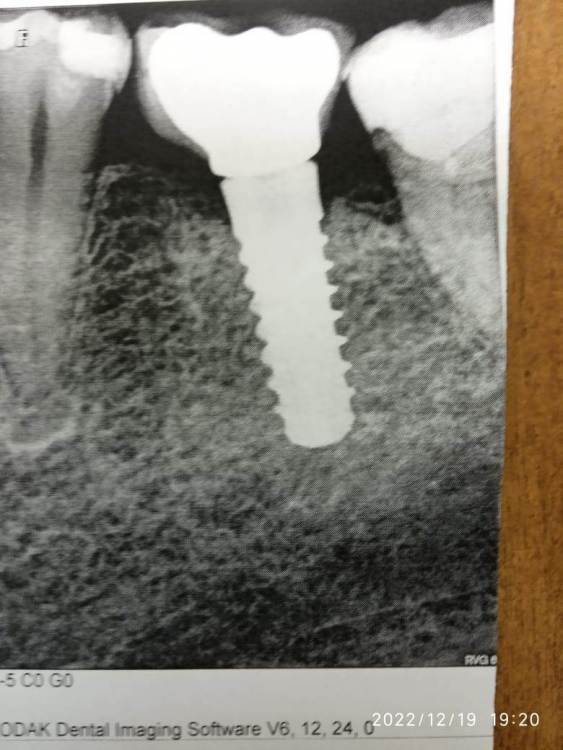

Julia Leykina Опубликовано 25 декабря, 2022 Поделиться Опубликовано 25 декабря, 2022 (изменено) Уважаемые доктора! У меня стоит имплантат испанской марки Klocrner модель SK2, расшатался винт, при попытке подобрать отвертку, он выкрутился, теперь винт и коронка отдельно (Подробнее писала о проблеме здесь, но с тех пор кое-что изменилось, и фокус моих поисков ориентирован на другое) . В РФ продукция этой марки не поставлялась, но я была на консультации в зубной клинике, где доктор мне любезно подобрала совместимую отвертку от старого комплекта Rusimplant. Вкручивать она отказалась без предварительных дорогостоящих процедур (по правилам клиники). Так что ищу этот набор (с динамометрическим ключом к нему), фото прилагаю, нужная отвёртка лежит сверху. Очень хотелось бы вкрутить до Нового года, потому что временная пломба (типа силиконовой нашлепки) уже один раз отвалилась (а прошло меньше недели с тех пор, как я осталась без коронки), сейчас новая пломба - не знаю, сколько продержится. Вдруг у вас есть нужный инструмент и вы согласитесь мне закрутить этот несчастный винтик? Для визуализации прилагаю фото рентгеновского снимка тоже. Также, как вариант, я бы купила нужный инструмент, если он вам не нужен и хотите от него избавиться, чтобы мне всё сделал врач в клинике, куда я обычно хожу. Я нахожусь в Москве, но ради решения проблемы готова приехать в любой граничащий с Московской областью город, райцентр, посёлок и т.п. Ну пожалуйста! Заранее благодарю. Изменено 25 декабря, 2022 пользователем Julia Leykina Ссылка на комментарий